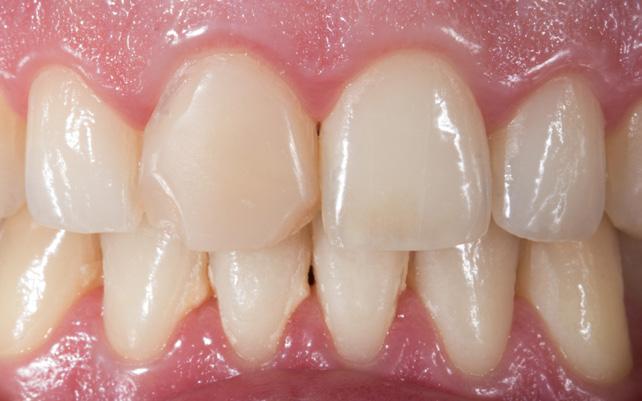

Restoring anterior teeth with large defects using composite seems to be quite challenging. With high-performance materials at hand and a systematic layering concept in mind, however, it is possible to produce highly aesthetic results in a reproducible way. The clinical case below is used to illustrate a dual-shade layering technique with CLEARFIL MAJESTY™ ES-2 Premium, a composite system with pre-defined colour combinations.

The patient, a young male, was unhappy with the appearance of his maxillary anterior teeth. Several years ago, his central incisors had been restored with composite. These existing restorations had defective and heavily discoloured margins, while their shade did not match the adjacent natural tooth structure. The maxillary lateral incisors were peg-shaped (microdontia). Economic considerations and the desire to save as much natural tooth structure as possible made the team decide to restore all four maxillary incisors with composite. CLEARFIL MAJESTY™ ES-2 Premium became the material of choice as it eliminates the need for complicated shade combination formulas and supports predictable outcomes.

We decided to restore the central incisors first and then focus on the lateral incisors. The tooth shade was determined using the VITA™ classical A1-D4 shade guide, while composite buttons were applied to the teeth to verify the determined shade combination. In order to simplify the restoration procedure, a palatal silicon index was produced before removing the existing restorations.

An adhesive (CLEARFIL™ Universal Bond Quick) was applied after selective etching of the enamel to achieve a strong bond. With the aid of the silicon index, it was easy to create the palatal shells of the restorations with CLEARFIL MAJESTY™ ES-2 Premium in the shade A3E (enamel), which matches the determined tooth shade A3. The dentin core was built up with the same composite in the recommended shade A3D (dentin), mamelons were modelled and some CLEARFIL MAJESTY™ ES-2 Premium in the shade WD added for the incisal halo, while some individual effects (like enamel cracks) were imitated with brown stain. The build-up was finalized in the interproximal and labial areas with composite in the shade A3E. Between the central incisors, a wedge was used to retract the papilla and facilitate the designing of the interproximal contact area. The finished and pre-polished restorations already had a natural appearance.